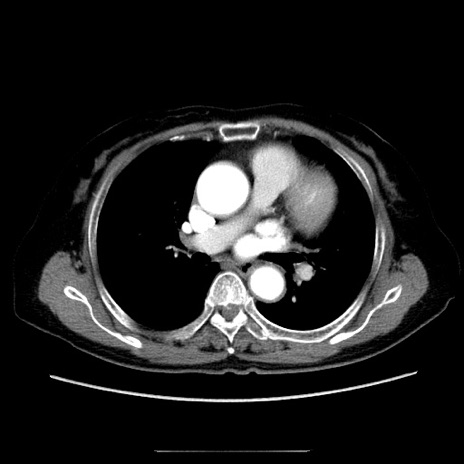

冠状断像

【症例】70歳代女性

【主訴】お腹が張る

【現病歴】1週間くらい前から腹部膨満の自覚あり。昨日夜から増悪したため、本日救急外来受診。

【身体所見】意識清明、BT 36.5℃、BP 165/106mmHg、HR 80bpm、SpO2 98%、腹部:膨満、軟、自発痛・圧痛なし、触診にて不快感あり、腸蠕動音:減弱

【データ】WBC 12600、CRP 1.04